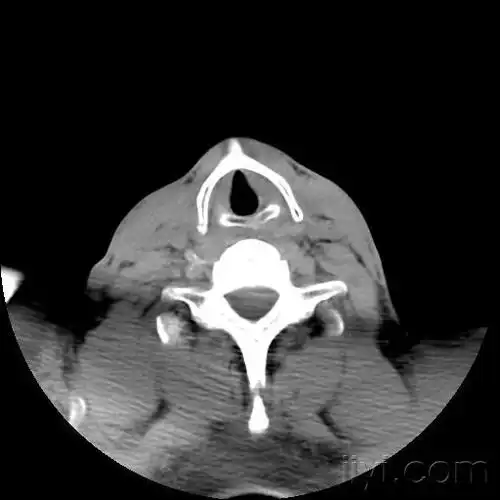

甲状软骨(常见病变,少见部位),请欣赏

6.颈动脉结节———c6.5. 环状软骨———c6.